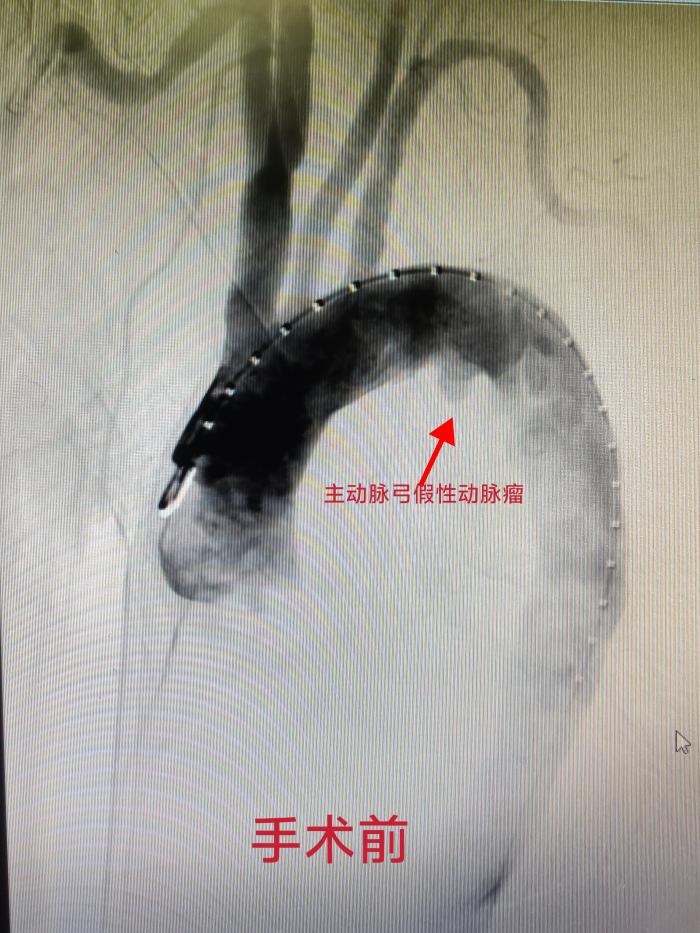

75岁的欧大爷因呼吸道疾病在当地进行CT检查时,意外发现主动脉弓下存在异常结节影。为寻求进一步诊治来到湘南学院附属医院就诊。介入血管外科龙文兴主任医师接诊后,通过详细检查,明确诊断欧大爷为主动脉弓假性动脉瘤,病情凶险,需尽快实施手术治疗。

龙文兴医生介绍,主动脉是心脏向全身供血的核心主干道,主动脉疾病起病急、风险高,被形象地称为体内“不定时炸弹”。其中主动脉弓假性动脉瘤尤为危重,欧大爷的假性动脉瘤动脉已经出现了破裂,靠周围血肿包绕,风险远高于真性动脉瘤。如同随时会爆裂的气球,一旦发生破裂,短时间内就会引发大出血,危及生命。

更为棘手的是,患者病变已累及左锁骨下动脉这一重要分支血管。常规手术不仅缺乏稳固的支架锚定区域,还极易出现支架与血管壁贴合不佳的“鸟嘴”现象,进而引发内漏,导致手术失败。

手术由龙文兴主任医师主刀,实施胸主动脉腔内介入修复术。凭借精湛的操作技术,结合新型支架的优异性能,手术顺利攻克各项难题。术后造影显示,血管破口被完全封堵,假腔无血流通过,支架贴壁牢固、无移位及内漏,重要分支血管供血通畅,手术取得圆满成功。